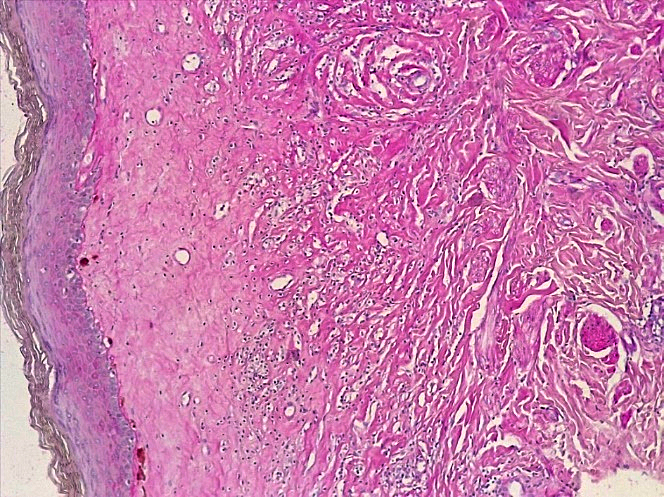

При проведении морфологического исследования тканей вульвы пациенток со склероатрофическим вариантом течения СЛВ также отмечалась резкая атрофия кожи за счет клеток эпидермиса и дермы, уменьшение клеточных слоев эпидермиса от 2–3 до 4–5 с участками повышенного ороговения (гипрекератоз). Количество базального слоя было снижено в разных случаях от 2–3 до 5–6 клеток в 1 мкм, что указывало на снижение функционального резерва эпидермиса. В случае длительного течения заболевания клетки базального слоя имели признаки дистрофии. В поверхностных слоях дермы отмечался фиброз с отложением масс гиалина, а также редукция кровеносных сосудов мелкого калибра, окруженных клеточным воспалительным инфильтратом из лимфоцитов и макрофагов (рис. 14–17).

Рис.14. Склероатрофический вариант СЛ. Резкая атрофия клеток эпидермиса с участками повышенного ороговения с развитием фиброзной соединительной ткани с лимфо-гистиоцитарной инфильтрацией дермы (окраска гематоксилином-эозином, х100).

Fig.14. Scleroatrophic variant of SL. Sharp atrophy of epidermal cells with areas of increased keratinization with the development of fibrous connective tissue with lympho-histiocytic infiltration of the dermis (hematoxylin-eosin staining, x 100)